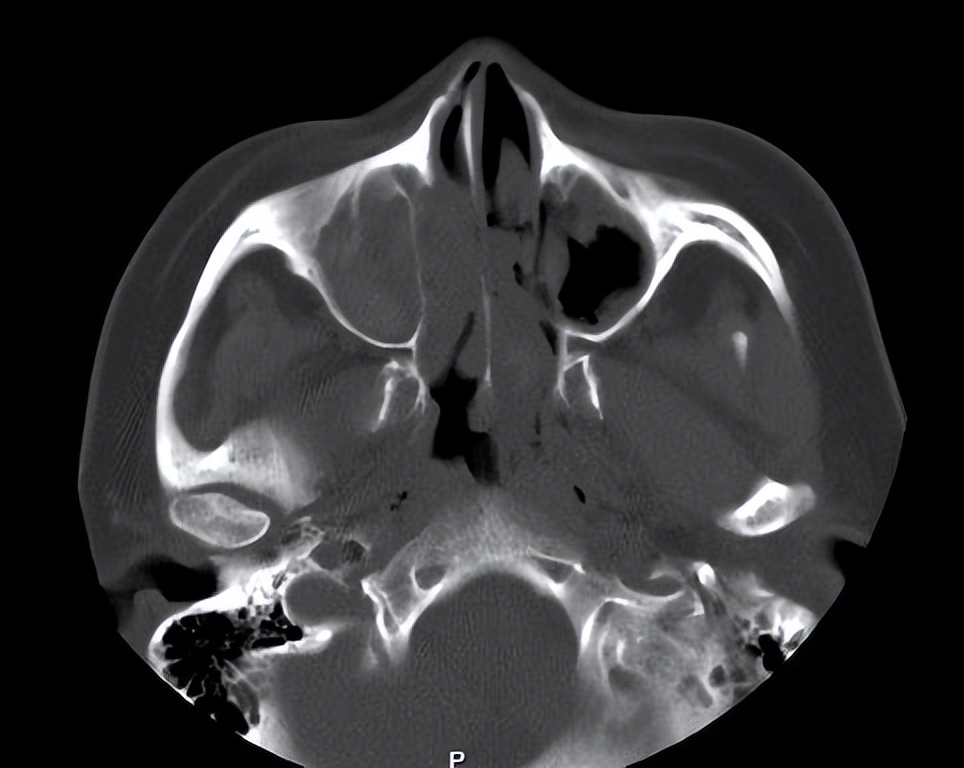

门诊鼻内镜检查提示:鼻窦炎伴鼻息肉。10年前曾在佛山第二人民医院行"鼻内镜鼻息肉切除+鼻中隔偏曲矫正手术"。但这次是明显的复发了,需要再次的手术治疗。

这次做了全麻鼻内镜鼻息肉切口鼻窦开放术,手术做的非常的顺利。但该手术术后需要进一步的治疗鼻炎,术后也对患者的鼻炎做了相应的治疗,再加上术后的治疗,只要鼻炎控制的好,一般复发的可能就会明显的减少。